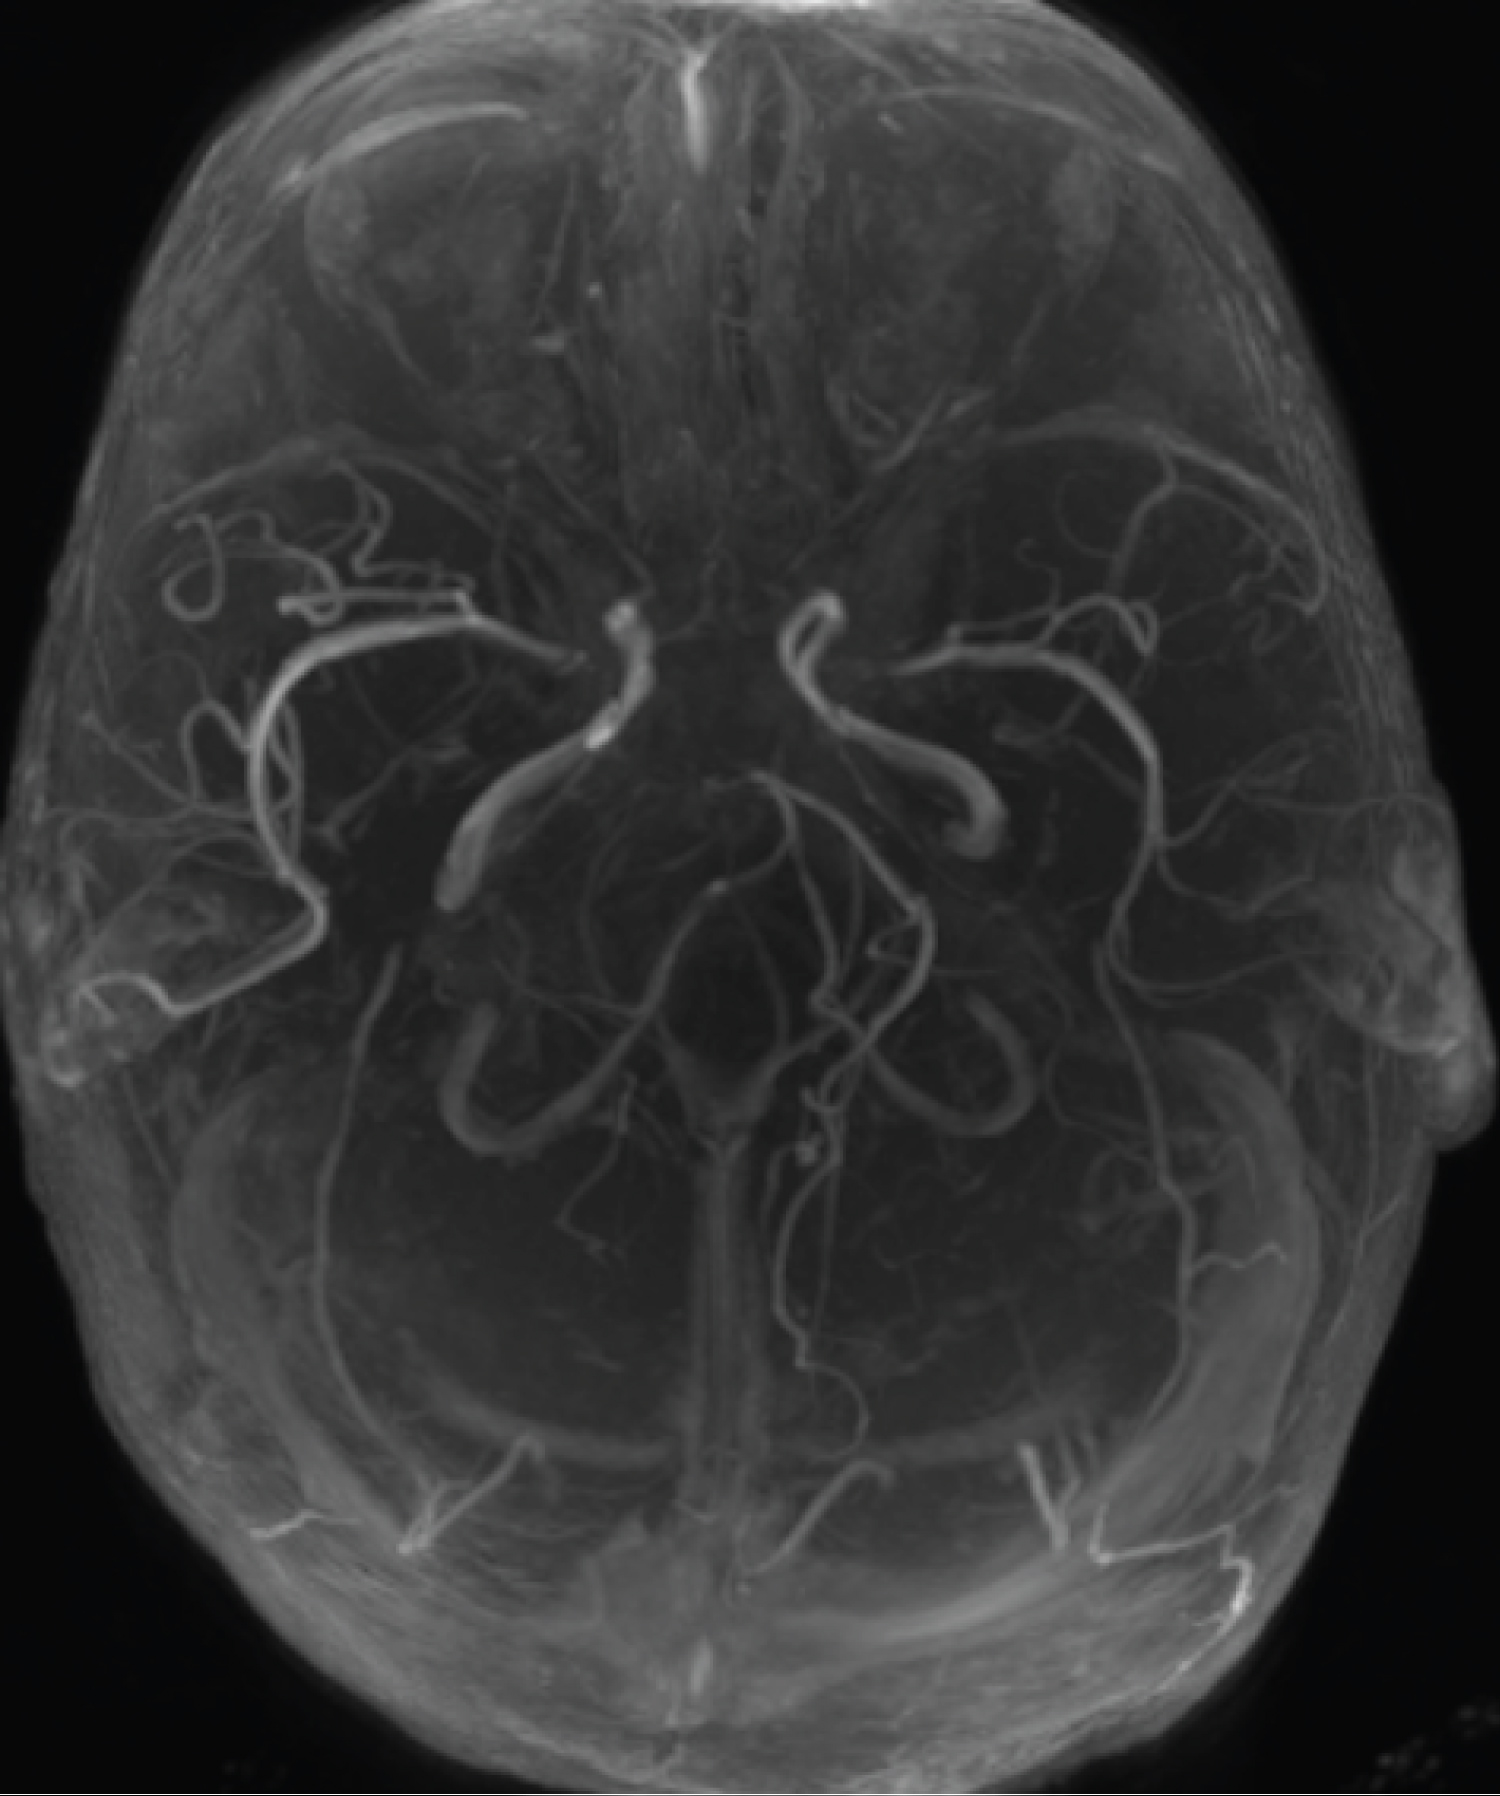

The patient is a 2-year-old child who referred to the pediatric emergency room due to loss of consciousness and suspected seizure symptoms. Also, the child's COVID-PCR test was reported positive 12 days before the visit, and the child had symptoms of cough and mild fever at the same time, which recovered at the same time. At the time of visit, the child was sleepy. He opened his eyes with painful stimulation and moved his right limbs less. Pupils were mid-sized, reactive and symmetrical. In the following examinations, there was no deviation in the eyes. Gag and corneal reflexes were normal. The child had spontaneous breathing and blood pressure and heart rate were normal. In the continuation of the history of the child, intolerance to food and milk was also mentioned. The initial blood sugar of the child was normal. After performing the initial measures, due to the unavailability of MRI, the child was subjected to brain CT scan. In the initial CT scan, the large size of the cerebral ventricles and hydrocephalus were mentioned for the child (Figure 1, Figure 2, Figure 3, Figure 4, Figure 5 and Figure 6). Due to hydrocephalus and clinical signs of increased ICP, the child was urgently transferred to the operating room, and while measuring ICP and sending a CSF sample, a ventriculoperitoneal shunt was implanted for the child. The child's icp was measured at 32 cmH2O. After the surgery, the child's level of consciousness improved relatively. The variables of the CSF sample sent were all in the normal range. The next day, the child underwent brain MRI and MRA. In the performed MRI, a clear signal change was seen in the frontal and occipital lobes, which is shown in photos No. 2, 3, 4, 5 and 6. According to the MRI, a biopsy was taken from the child's right frontal lobe for a definitive diagnosis. Immunohistochemical examination revealed the demyelinating nature of the specimen, in which extensive infiltration of basal macrophages and activated microglial cells was seen, while axons were largely preserved. No sign of vasculitis was seen in the examination of the sample. In this way, the result of the examination of the brain sample confirmed ADEM. With this diagnosis, the child was treated with corticosteroids and IVIG. The disease responded dramatically to the treatment. All the child's symptoms improved within two days and the child's level of consciousness reached its normal range. Finally, the child was discharged from the hospital after a week with a good general condition.

Figure 6: MRA showing normal vascularity. View Figure 6